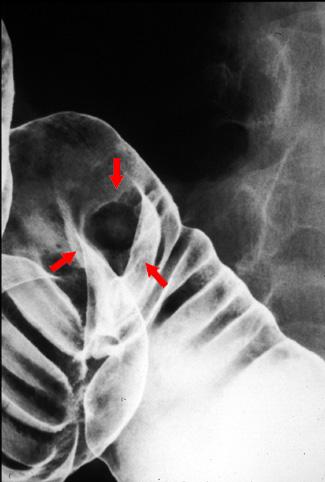

Criteria of Hist.ClassificationMalignant epithelial tumor/Adenocarcinoma

LocationLarge intestine(Colon)/Transverse colon

Technique, MethodX-ray

Macroscopic TypesType 1 Protuberant (polypoed) type/

Size1 - 9

Depth of Tumor Invasionsubserosa (subadventitia)